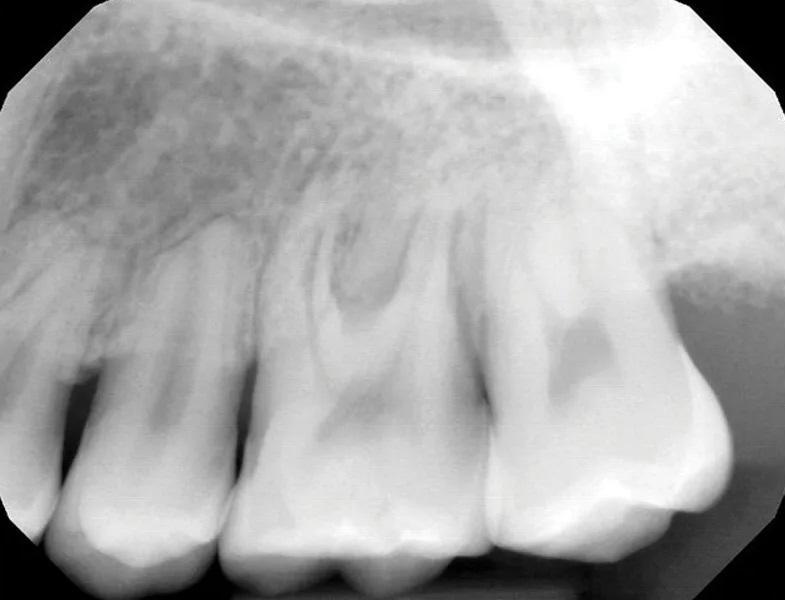

Фото 3. Предоперационный периапикальный рентгеновский снимок, показывающий короткие, затупленные корни зубов № 2.4, с апикальной резорбцией корня зуба № 2.5 и дистального щечного корня зуба № 2.6. Отмечалась тесная близость корней зубов №№ 2.6 и 2.7 с умеренным образованием интерпроксимальных кариозных полостей. Рентгенологическое просветление в основном затрагивало фуркацию зуба № 2.6.